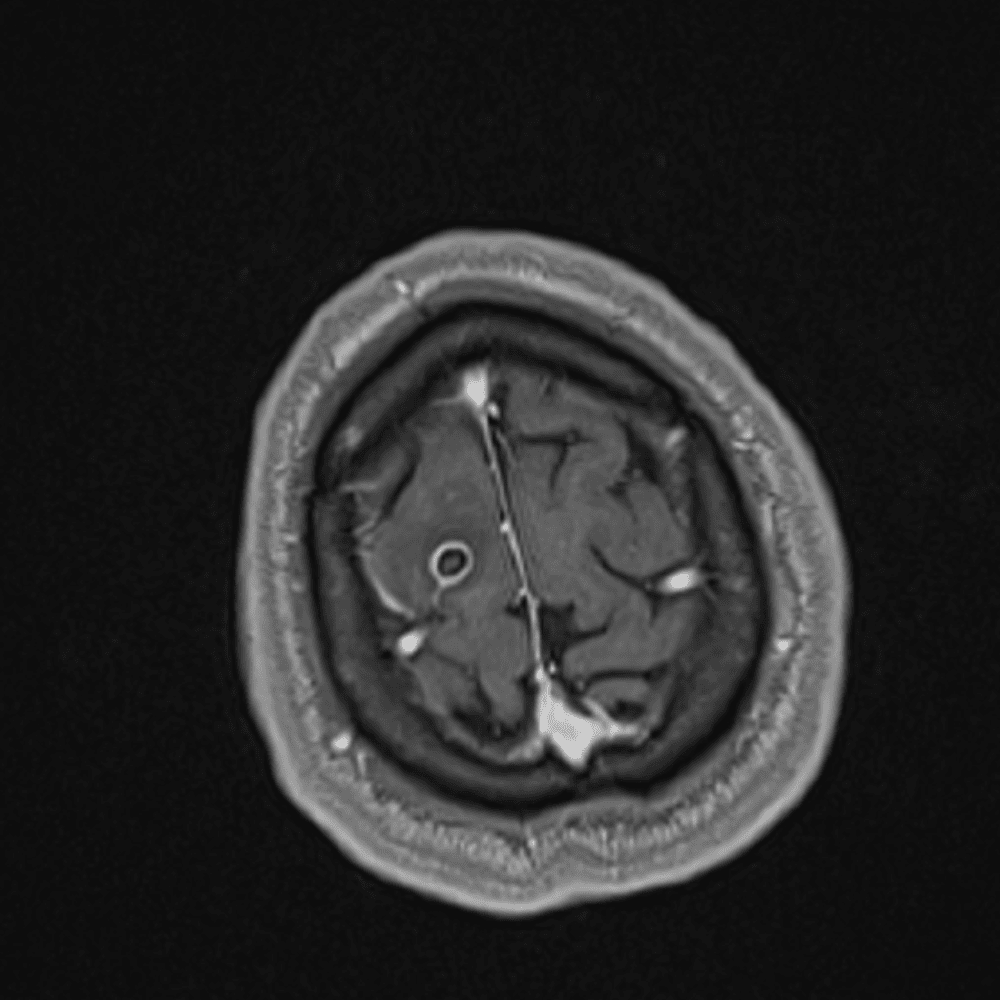

๋‹น์ง ์‹œ ํ”ํžˆ ๋ณผ ์ˆ˜ ์žˆ๋Š” ์‚ฌ๋ก€์˜ ์ „ํ˜•์ ์ธ ์˜ˆ๋ฅผ ํฌํ•จํ•ฉ๋‹ˆ๋‹ค.

39 ์‚ฌ๋ก€

์—ฐ์Šต

๋ฏธ๋ฌ˜ํ•˜๊ฑฐ๋‚˜ ์–ด๋ ค์šด ์‚ฌ๋ก€์™€ ์ผ๋ถ€ ์ •์ƒ ์‚ฌ๋ก€๋ฅผ ํฌํ•จํ•˜์—ฌ ๋‹น์ง์„ ์‹œ๋ฎฌ๋ ˆ์ด์…˜ํ•ฉ๋‹ˆ๋‹ค.

50 ์‚ฌ๋ก€